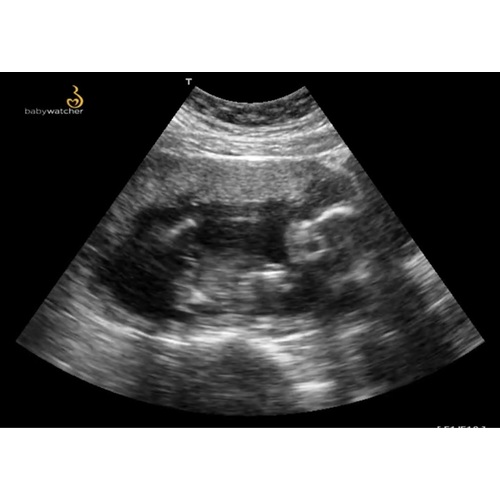

Hi ik heb de baby watcher 3 dagen gehad. Je moet niet het beste kwaliteit verwachten. Je kan niet alles duidelijk er mee zien je kan zien dat je kleine lekker beweegt en met geluk kan je het hartje zien. Bij mij was er gedoe bij het leveren op de dag zelf kregen we te horen dat die niet kwam en toen ik hem wou annuleren kon de baby watcher ineens op de post.

Mijn ervaring is als je zelf een goeie laptop hebt neem daar het pakket op zodat wellicht je beeld veel beter is je krijg hier best oudere laptops bij en de beeld kwaliteit is gewoon niet het beste. Als ik het had geweten had ik me eigen laptop genomen

Ja klopt, die krijg je er bij maar je kan ook aangegeven voor je eigen laptop tegebruiken 馃 hou er wel rekenschap mee dat melde ze mij later pas toen ik belde dat kwaliteit minder was als je plus size bent de kwaliteit slechter is.